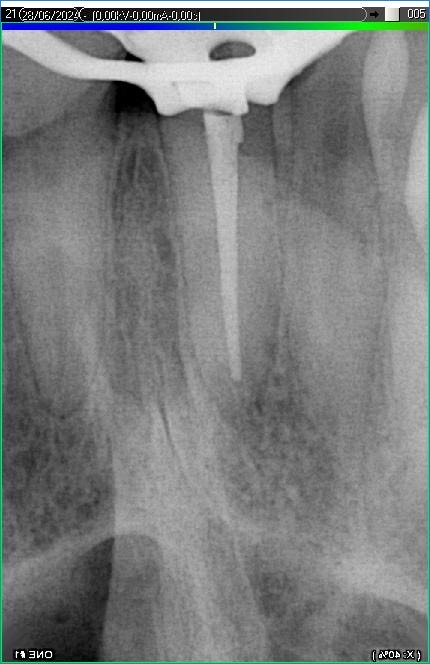

Вилучення інструменту з каналів зуба